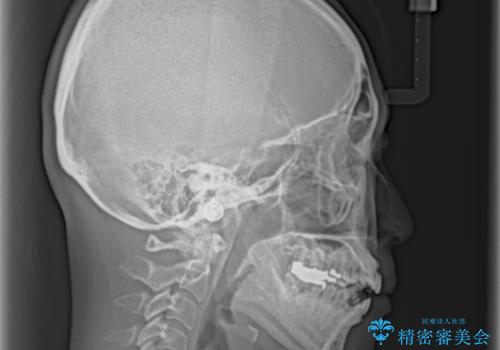

極端な上下前歯の開咬を改善 オープンバイトのインビザライン矯正

- 上下前歯の隙間を気にして来院された患者様です。

開咬の治療は、前歯を閉じるように動かすとともに、上下臼歯を圧下(骨内にめり込ませる)させることで進めて行きます。

インビザラインは臼歯の圧下を効果的に行えるため、インビザラインを用いて矯正治療を行うこととしました。

また、下顎大臼歯に根管治療が必要な歯があるため、矯正治療と並行して治療を行い、矯正後に補綴治療することとしました。

治療前に、いくらインビザライン矯正がオープンバイトを得意としているとは言え、さすがに限界があるだろうと思っておりましたが、前歯でレタスが噛めるまで改善することができました。